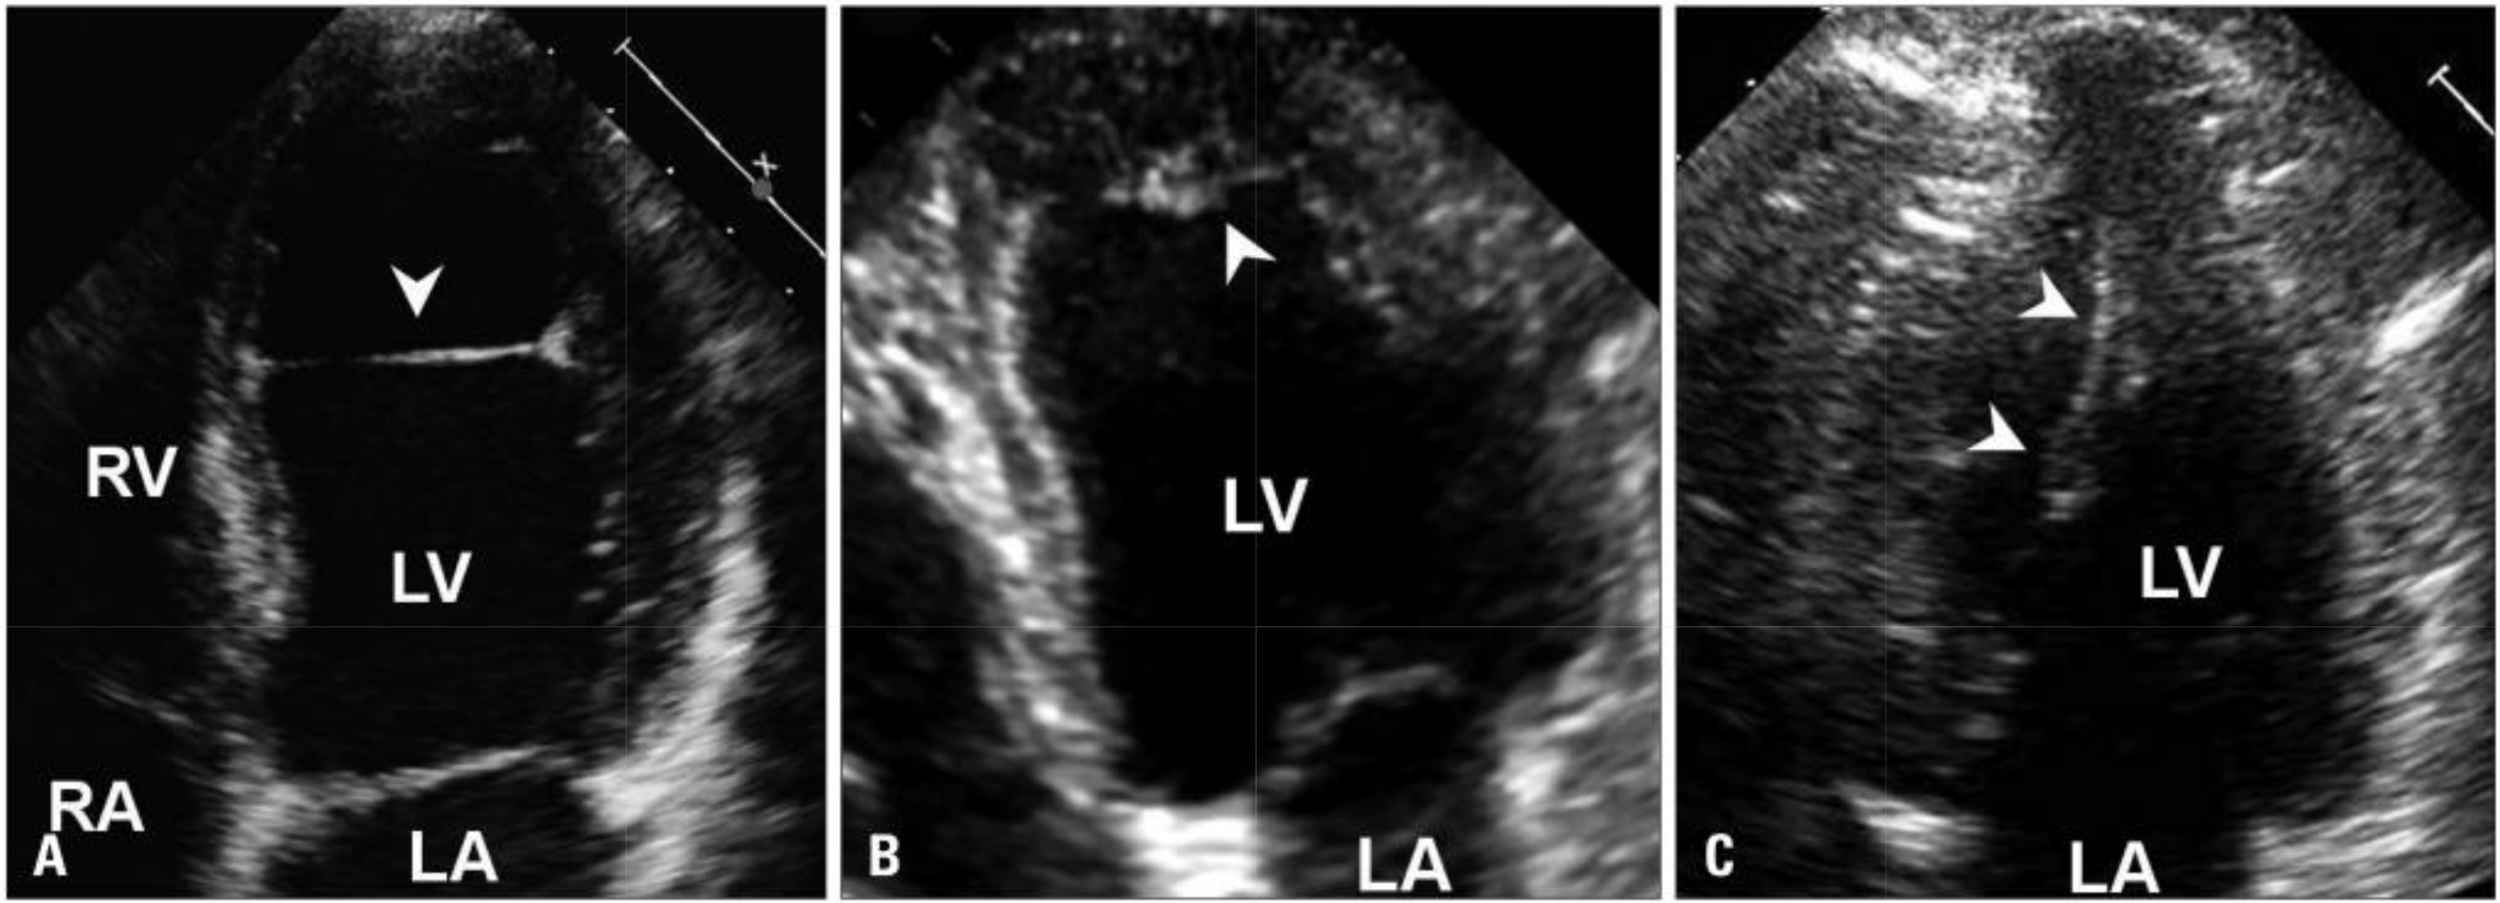

False Tendon

• Found in over 50% of LV in autopsy studies

• Unlike trabeculations, they traverse the LV cavity

• Echo free space on both sides

• Taut in diastole, laxe in systole

• Can have broad base attachment

• Can rupture in MI or spont

LV Bands

Muscular Band

Papillary Muscle